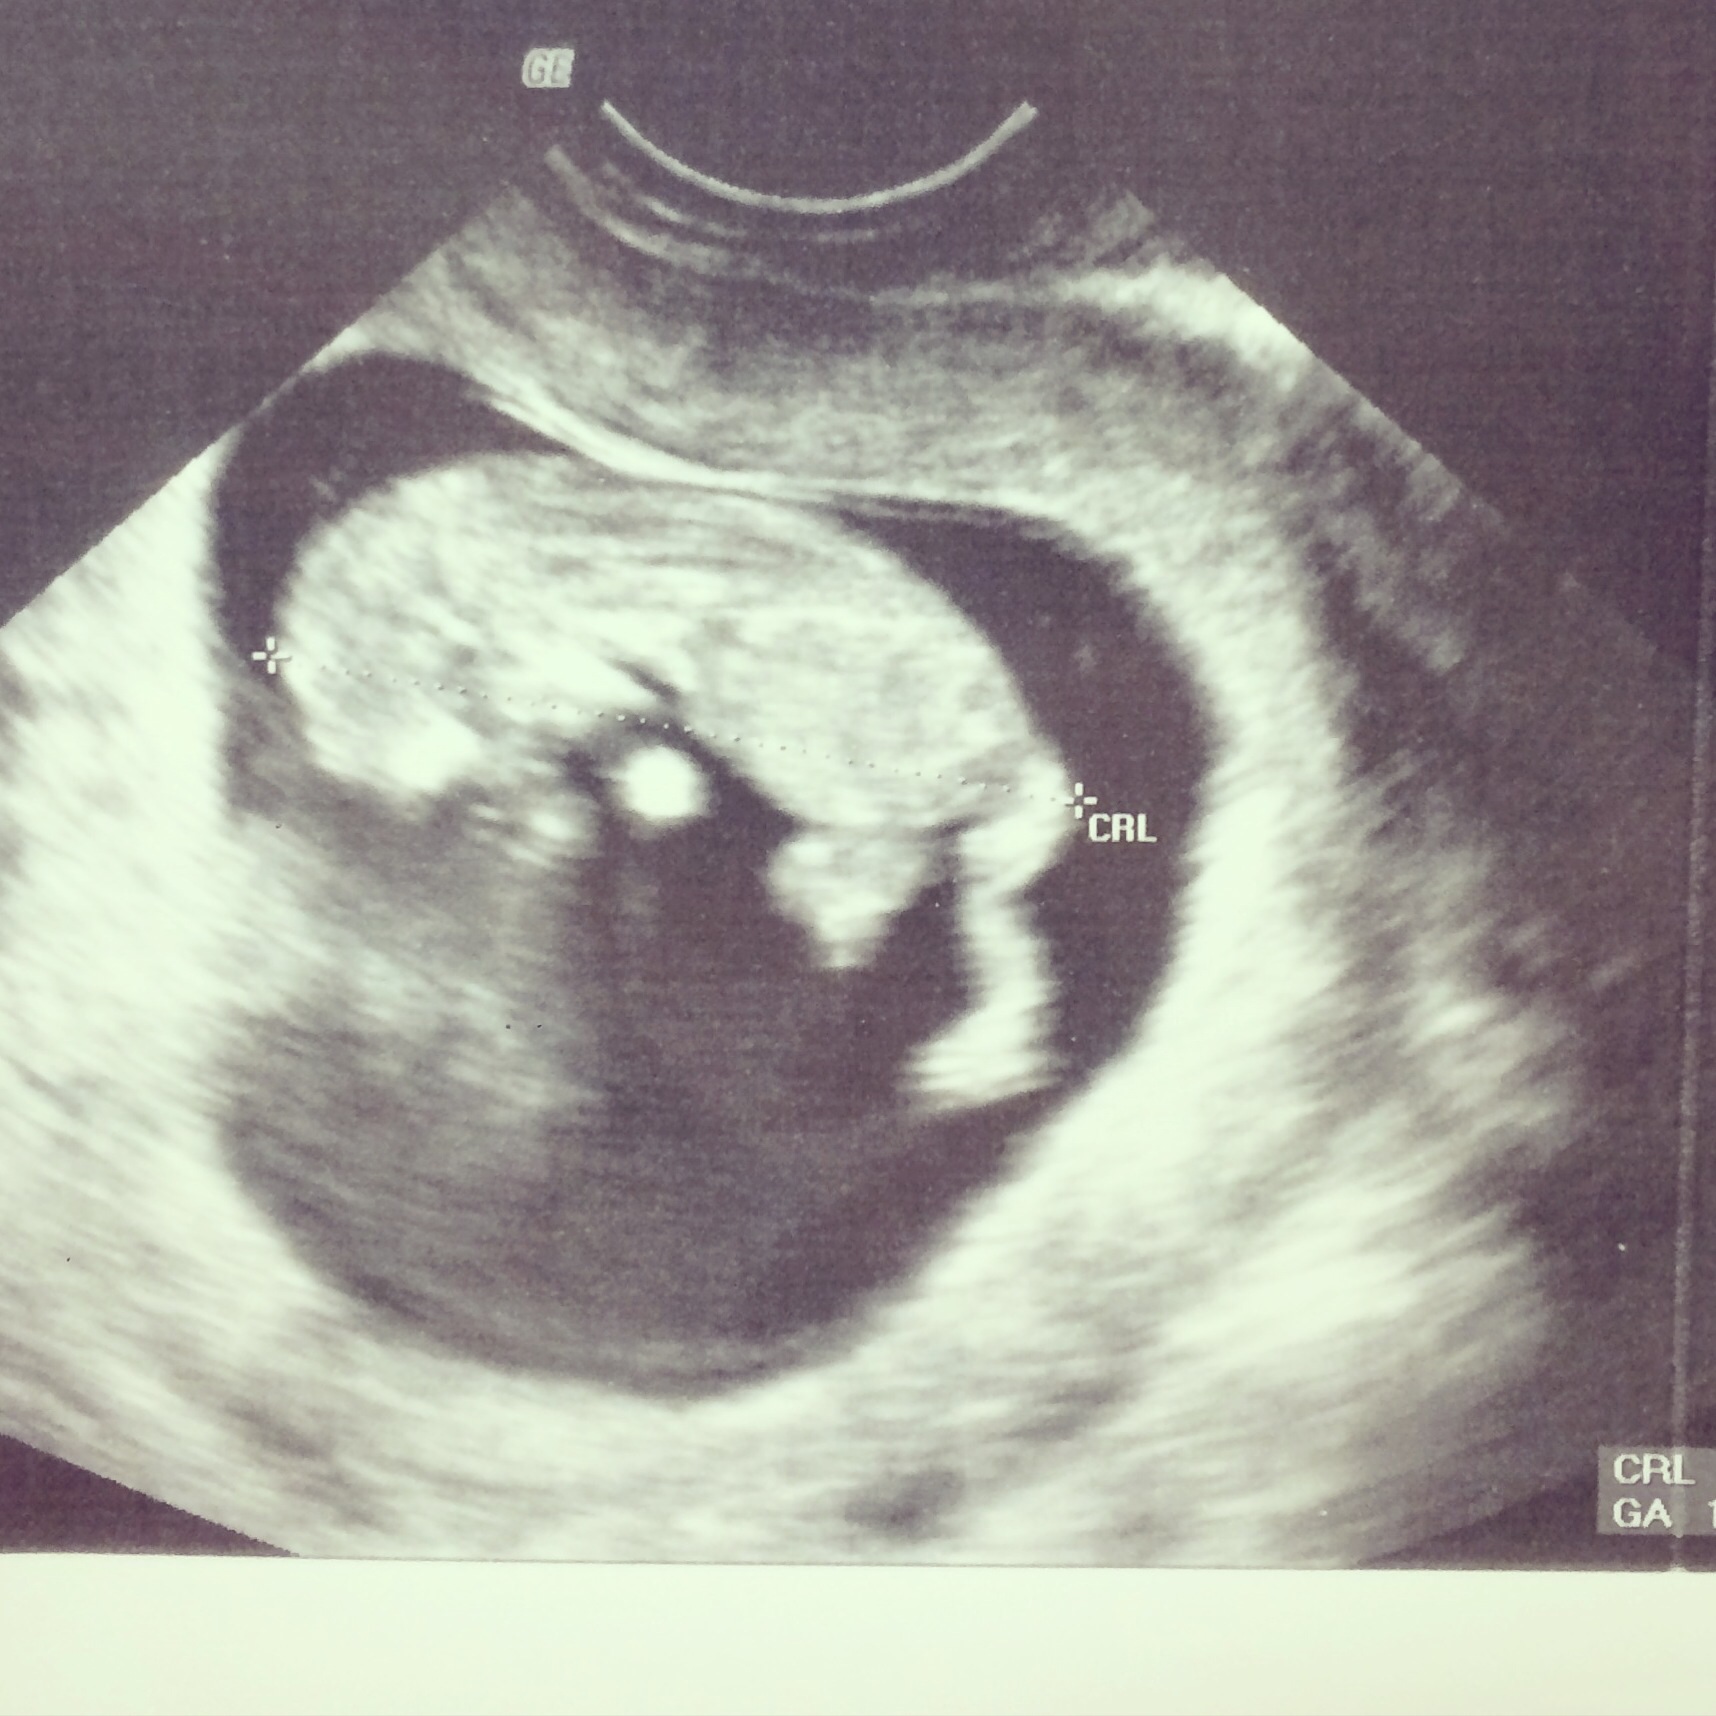

This is mine at 11 weeks. We could see arms, legs, jaw, even fingers and toes.

image.jpg